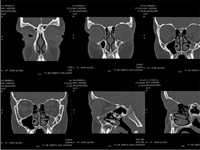

La tomografía computerizada (TC) de órbita (

Figura 1 y

Figura 2) evidenciaba una lesión ocupante de espacio de densidad de partes blandas de 3 centímetros de diámetro localizada a nivel superomedial de la órbita izquierda y que desplazaba el globo ocular anterolateralmente, así como al recto interno y el recto-oblicuo superior. No se apreciaban lesiones óseas, ni afectación de senos paranasales ni frontales.

Figura 2. TC órbita (coronal y sagital de órbita izquierda).